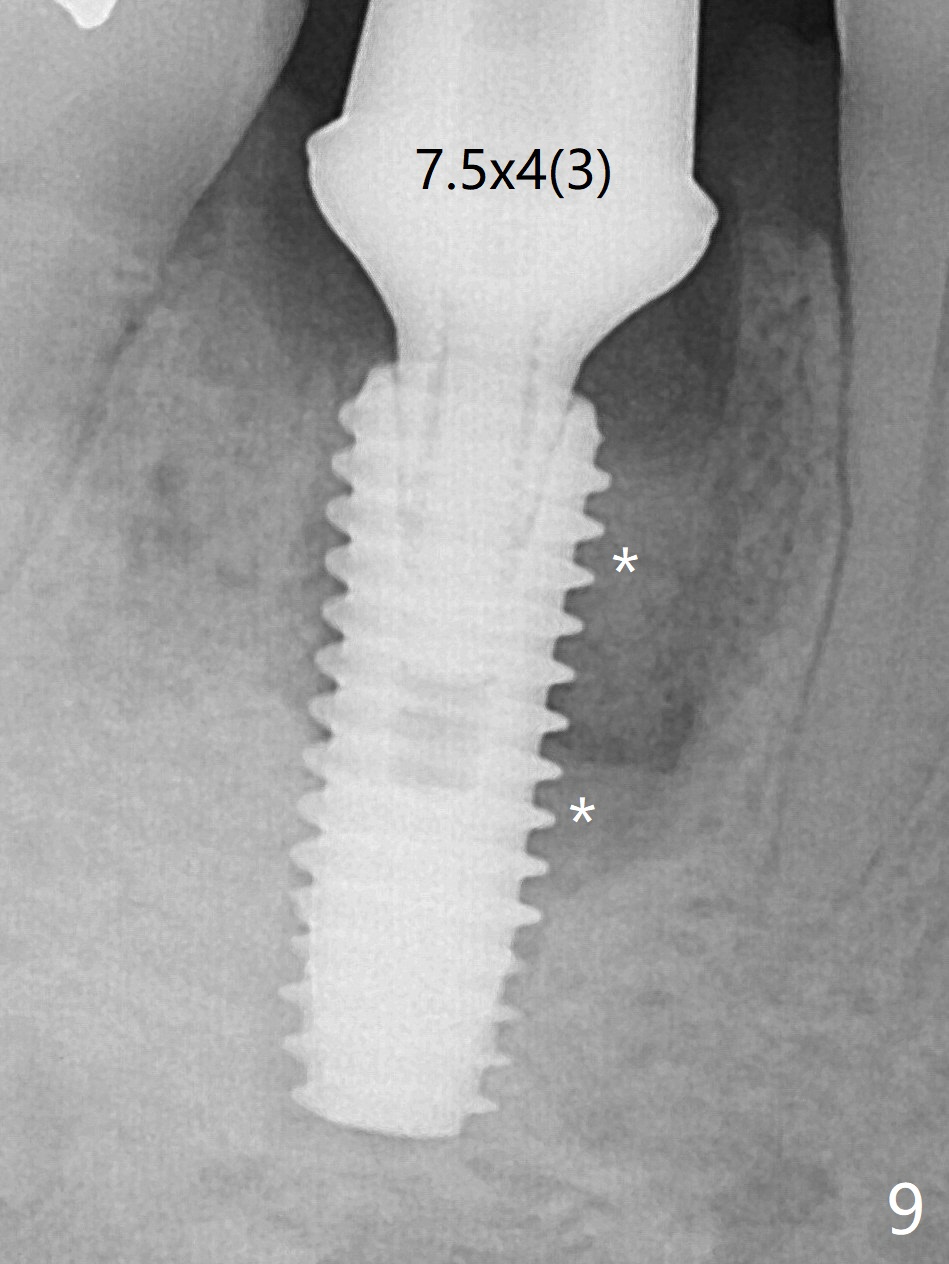

Preop oral Amoxicillin seems to be associated with reduction in the buccal and lingual (Fig.3 arrow) fistulae at #30, but there is mesiobuccal swelling (Fig.1 *) with 7 mm pocket (Fig.2). Osteotomy is initiated in the middle of the septum (Fig.3-5 S). As the osteotomy increases, it shifts mesially (Fig.6 arrow). Guided surgery is able to reduce shifting. A 5x13 mm implant is not seated completely (Fig.7) apparently due to osteotomy shifting. After removal of the bone from the osteotomy distally, the implant remains unseated with lower torque value (Fig.8). Following reuse of the 4.3 mm drill deeper by 1-2 mm, the implant is seated to a satisfactory depth (Fig.9 with increase in torque to 50 Ncm) with placement of Vera Graft (*) and a 7.5x4(3) mm abutment. After a second round of allograft placement (Fig.10 *), the implant is found to be 4 mm from the IAC. At the later stage of osteotomy, the coronal end of the septum is destroyed with loss of osteotomy depth landmark. It is apparent that the soft tissue landmark may be more reliable. The implant threads appear to be covered by the bone graft 3.5 months postop (Fig.11). The abutment is changed to 6.5x5(3) mm one before impression with minor margin prep. The bone density seems to increase 5 months postop, i.e., immediately post cementation (Fig.12) and 10 months postop (5 months post cementation (after retightening abutment), Fig.13 (*)). Periimplantitis develops mesiobuccally, consistent with bone loss 1 year 7 months post cementation (Fig.14 *); the implant seems to have been buccally placed. Bone graft is necessary with PRF or GEM21S if the vein is small and 6-month membrane with a hole around a 7.5x4(4) cemented abutment for easy wound closure. Take 5x5 CM CBCT to determine which wall has defect, buccal or lingual. Check mesial contact. If so, remove the crown, reseat the abutment (possible incomplete seating) and re-impress after bone graft.